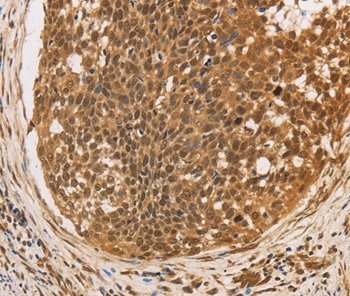

Immunohistochemical analysis of paraffin-embedded Human cervical cancer tissue using #36381 at dilution 1/20.

Immunohistochemical analysis of paraffin-embedded Human tonsil tissue using #36381 at dilution 1/20.